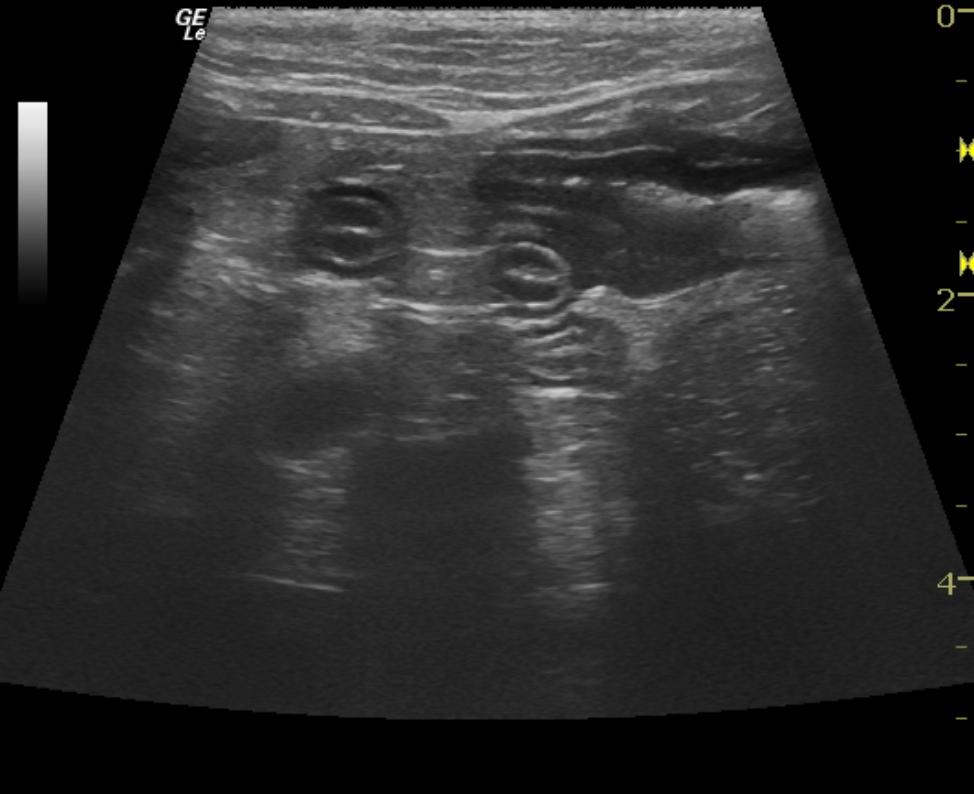

A 16-year-old MN DSH cat was presented for weight loss, decreased appetite, decreased drinking, and constipation. Physical exam was unremarkable other than poor body condition and palpably thickened intestines. CBC revealed neutrophilia. Blood chemistry showed hyperamylasemia and the T4 was within normal limits. Urinalysis showed a cloudy, amber appearance, hematuria, and a large number of RBCs. Urine microalbumin was within normal limits and the urine culture did not yield any growth.